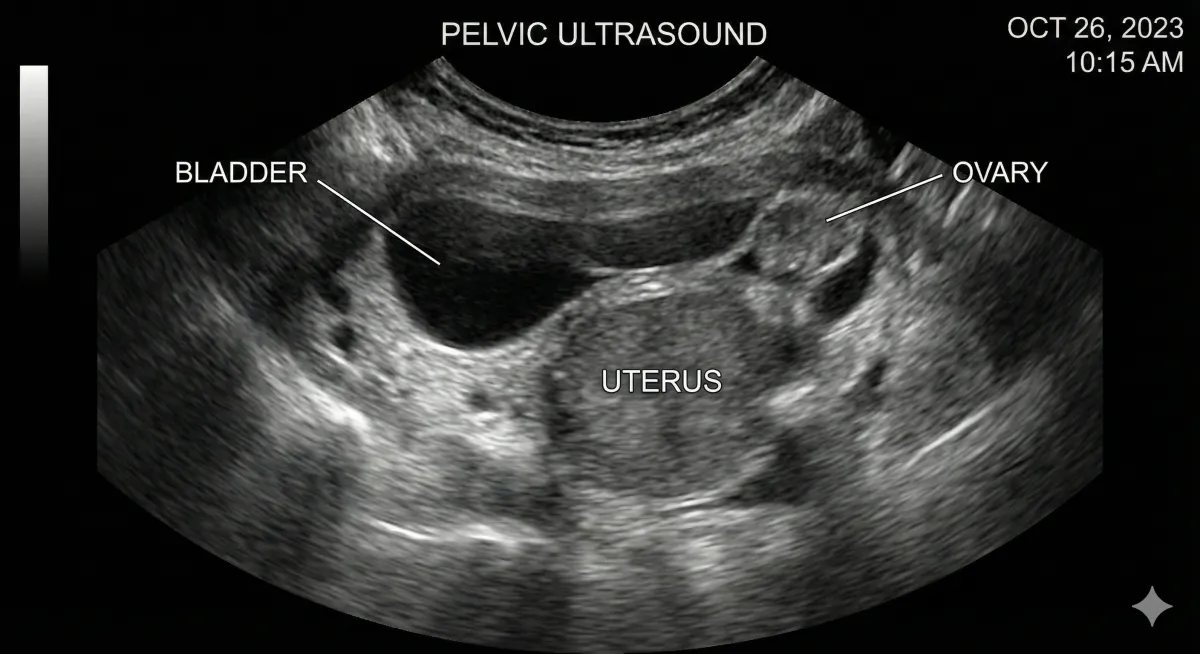

A pelvic ultrasound is a safe, common test used to look at your uterus, ovaries, cervix, and bladder. It uses sound waves, not radiation, and is generally well tolerated—even if you feel nervous beforehand.

Done with an empty bladder and gives clearer images of the uterus and ovaries.